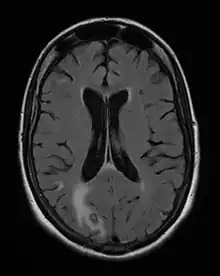

Acute toxoplasmosis is often asymptomatic in healthy adults.[13][14] However, symptoms may manifest and are often influenza-like: swollen lymph nodes, headaches, fever, and fatigue,[15] or muscle aches and pains that last for a month or more. It is rare for a human with a fully functioning immune system to develop severe symptoms following infection. People with weakened immune systems are likely to experience headache, confusion, poor coordination, seizures, lung problems that may resemble tuberculosis or Pneumocystis jirovecii pneumonia (a common opportunistic infection that occurs in people with AIDS), or chorioretinitis caused by severe inflammation of the retina (ocular toxoplasmosis).[15] Young children and immunocompromised people, such as those with HIV/AIDS, those taking certain types of chemotherapy, or those who have recently received an organ transplant, may develop severe toxoplasmosis. This can cause damage to the brain (encephalitis) or the eyes (necrotizing retinochoroiditis).[16] Infants infected via placental transmission may be born with either of these problems, or with nasal malformations, although these complications are rare in newborns. The toxoplasmic trophozoites causing acute toxoplasmosis are referred to as tachyzoites, and are typically found in various tissues and body fluids, but rarely in blood or cerebrospinal fluid.[17]

Due to the absence of obvious symptoms,[13][14] hosts easily become infected with T. gondii and develop toxoplasmosis without knowing it. Although mild, flu-like symptoms occasionally occur during the first few weeks following exposure, infection with T. gondii produces no readily observable symptoms in healthy human adults.[7][20] In most immunocompetent people, the infection enters a latent phase, during which only bradyzoites (in tissue cysts) are present;[21] these tissue cysts and even lesions can occur in the retinas, alveolar lining of the lungs (where an acute infection may mimic a Pneumocystis jirovecii infection), heart, skeletal muscle, and the central nervous system (CNS), including the brain.[22] Cysts form in the CNS (brain tissue) upon infection with T. gondii and persist for the lifetime of the host.[23] Most infants who are infected while in the womb have no symptoms at birth, but may develop symptoms later in life.[24]

Toxoplasmosis in humans is diagnosed through biological, serological, histological, or molecular methods, or by some combination of the above.[62] Toxoplasmosis can be difficult to distinguish from primary central nervous system lymphoma. Its symptoms mimic several other infectious diseases, so clinical signs are non-specific and are not sufficiently characteristic for a definite diagnosis. A failed trial of antimicrobial therapy (pyrimethamine, sulfadiazine, and folinic acid (USAN: leucovorin)), makes an alternative diagnosis more likely.